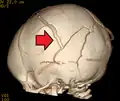

| An intraparenchymal bleed with overlying skull fracture from shaken baby syndrome | |

A skull fracture from abusive head trauma in an infant -

3D CT reconstruction showing a skull fracture in an infant -

3D CT reconstruction showing a skull fracture in an infant